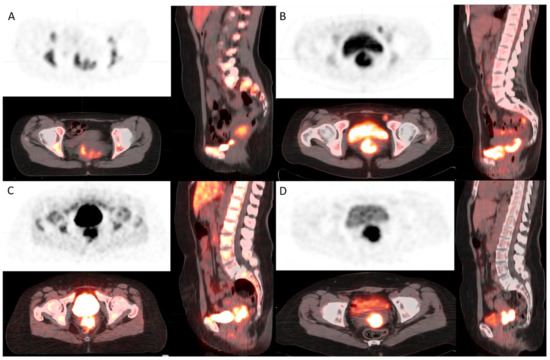

Differences between [18F]FLT and [18F]FDG Uptake in PET/CT Imaging in CC Depend on Vaginal Bacteriology

| SUV max FLT | 34 | 7.7 | 7.46 | 3.1 | 16.5 | 10.7 |

| SUV mean FLT | 34 | 4.8 | 4.4 | 1.9 | 9.9 | 6.8 |

| SUVmin FLT | 34 | 3.2 | 3.5 | 1.3 | 8.9 | 4.6 |

| SUV max FDG | 34 | 11.7 | 11.8 | 5.3 | 24.7 | 4.2 |

| SUV mean FDG | 34 | 6.9 | 7.3 | 2.6 | 14.7 | 2.6 |

| SUVmin FDG | 34 | 5.1 | 5.1 | 2.3 | 10.6 | 1.8 |